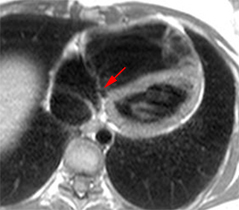

– Insuffisance mitrale : intérêt limité de l’IRM, quoique des approches quantitatives soient possibles.

– Rétrécissement mitral : intérêt limité de l’IRM.